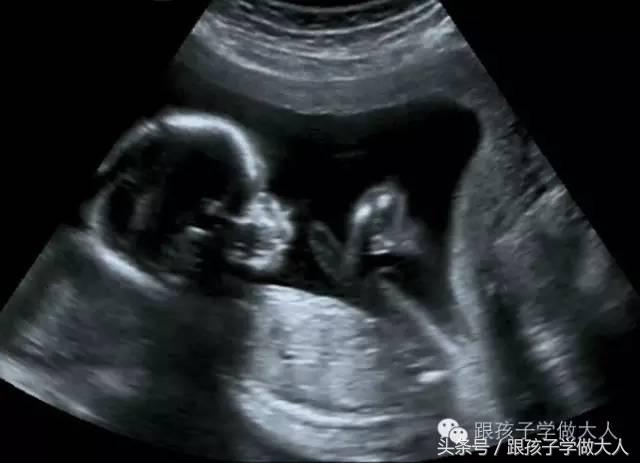

2、孕中、晚期胎宝宝各器官已经形成,B超检查还是相对比较安全的。从孕20周起,准妈应定期进行B超检查:

①孕20-24周左右,观察胎头,脊柱、心脏、肺、胃肠、双肾、膀胱、外生殖器、四肢,此时是四肢等大的畸形检查的最佳时期;

②孕24一32周,重点观察胎宝宝鼻唇部,心脏,可发现鼻唇部、心脏的畸形。

③(孕37一41周)的B超检查,注重胎位、脐带、羊水、胎盘分期、估计胎宝宝大小,可通过脐血流了解胎宝宝安危。